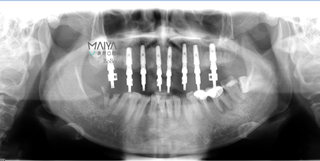

根据郄女士的口腔内实际情况和她本人对牙齿美观/恢复咀嚼功能的要求,2015年底,麦芽口腔种植医师团队为其实施了半口无牙即刻种植、即刻修复技术。

种植体的植入

术后口腔ct全景片